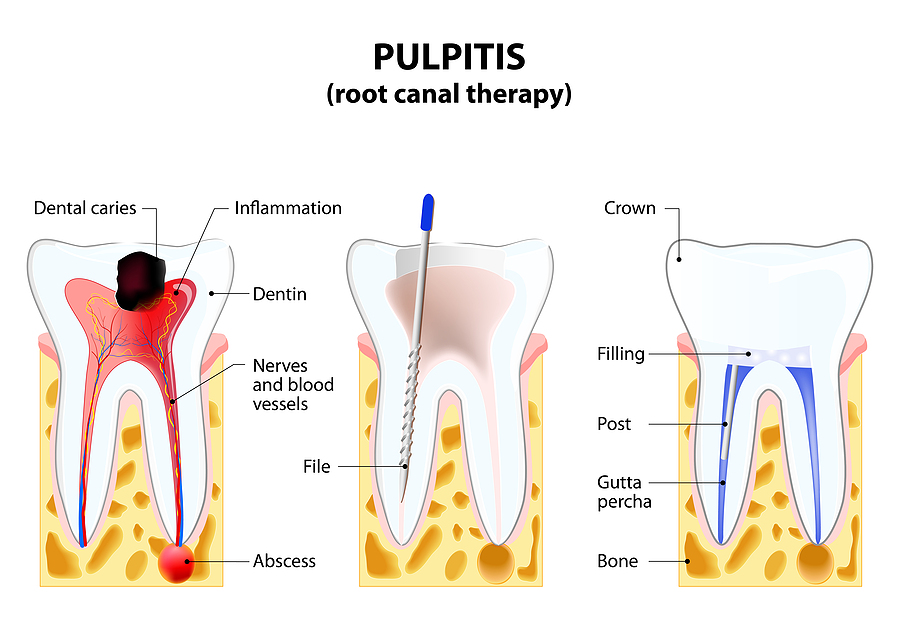

The Importance of Root Canals in Maintaining Your Oral Health

When a tooth becomes severely decayed or infected, a root canal is often the best treatment to save it. This procedure removes the infected pulp inside the tooth, cleans the canal, and seals it to prevent further issues. If you are experiencing persistent tooth pain or sensitivity, root canals in Stratford, CT, might be your […]